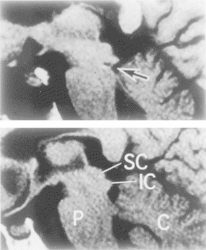

Note: Loss of speech understanding in instances of closed

head injury was attributed to trauma caused by impact

from the cerebellar tentorium in 3 cases

.

If traumatic injury of the inferior colliculi is seen with MRI

(as in the case of the ski accident), decreased activity with

fMRI would also be anticipated, and could be compared

with activity levels determined in individuals with

developmental language disorders.